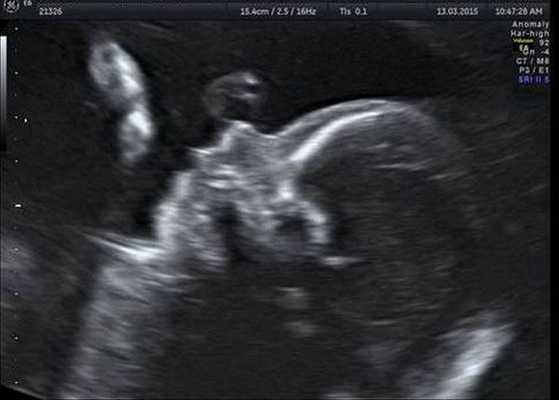

На современном этапе развития ультразвуковой диагностики в большинстве случаев шизэнцефалия диагностируется антенатально во время планового скрининга беременности. Намного лучше визуализируется расщелина сомкнутого типа, тогда как открытая шизэнцефалия может остаться незамеченной. Для постнатального подтверждения диагноза детскому неврологу требуются следующие методы исследования:

- МРТ головного мозга. Магнитно-резонансная томография — безопасный метод даже для новорожденных. При 1 типе аномалии обнаруживается выпячивание стенки желудочков с узким каналом. 2 тип характеризуется открытой расщелиной, которая заполнена цереброспинальной жидкостью. При необходимости выполняется МРТ мозговых сосудов.

- Нейросонография. УЗИ головного мозга используется как альтернатива МРТ у новорожденных, младенцев до закрытия большого родничка. Сонография достаточно информативна при шизэнцефалии I типа. Метод также применяется для выявления сопутствующих аномалий строения церебральных структур. Для уточнения диагноза нейросонография дополняется УЗДГ церебральных сосудов.

2. Пренатальная диагностика шизэнцефалии/ А.Е. Волков, Е.Н. Андреева// SonoAce Ultrasound. — 2010. — №21.

4. Шизэнцефалия, тип II: случай пренатальной диагностики/ Е.Н. Андреева// Пренатальная диагностика. — 2008. — №4.